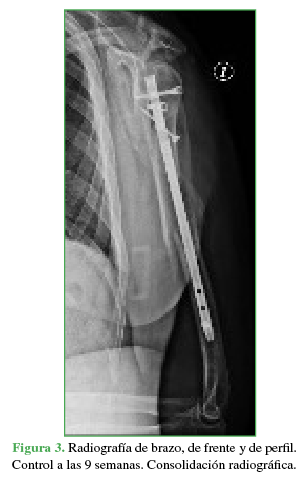

Durante el seguimiento, se comprobó la mejoría funcional progresiva y constante en la flexión activa del pulgar e índice. La fractura consolidó a las nueve semanas de la intervención (Figura 3).

Cuatro semanas después de la operación, se realizó un estudio neurofisiológico que incluyó una electromiografía y pruebas de velocidades de la conducción nerviosa para evaluar el grado de lesión y el pronóstico definitivo. Se confirmó una lesión axonal en continuidad tipo II-III de Sunderland, de los fascículos correspondientes al flexor largo del pulgar y el flexor profundo del índice con abundante reinervación.